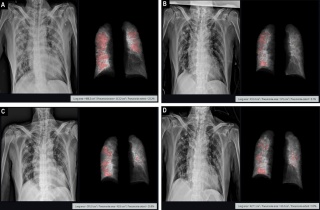

Äڷγª19 Æó·Å Á¤·®È¡¤»ç¸Á À§Çè ¿¹Ãø ±â¼ú ÀÔÁõ

[µ¥Àϸ®¸Þµð ±¸±³À± ±âÀÚ] ¸ÞµðÄþÆÀÌÇÇ(´ëÇ¥ ¹Ú»óÁØ)°¡ ÀÚ»ç ¼Ö·ç¼Ç 'Ƽ¼Á'À» Ȱ¿ëÇØ ¿¢½º·¹ÀÌ ¿µ»ó¿¡¼ ½ÅÁ¾ Äڷγª¹ÙÀÌ·¯½º °¨¿°Áõ(Äڷγª19) Æó·ÅÀ» Á¤·®ÈÇÑ ¿¬±¸ ³í¹®À» ÀÇÇÐ ±¹Á¦ÇмúÁö ‘PLOS ONE’¿¡ °ÔÀçÇß´Ù°í 27ÀÏ ¹àÇû´Ù. ¸ÞµðÄþÆÀÌÇÇ´Â °ü°èÀÚ´Â "Ƽ¼ÁÀ» Ȱ¿ëÇØ Äڷγª19 ÈäºÎ ¿¢½º·¹ÀÌ »çÁø¿¡¼ Æó ¼Õ»ó Á¤µµ¸¦ ¼öÄ¡·Î ºÐ¼®ÇÏ°í º´Áõ ÃßÀ̸¦ °èÃþÈÇØ »ç¸Á À§Çèµµ¸¦ ¿¹ÃøÇÒ ¼ö ÀÖ´Ù´Â °¡´É¼ºÀ» È®ÀÎÇß´Ù"°í ¸»Çß´Ù. Ƽ¼ÁÀº Äڷγª19...